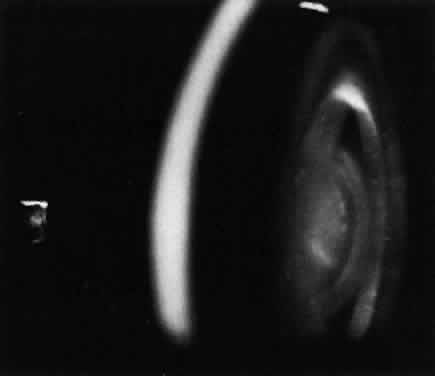

Type B NPD has a variable phenotype, with only visceral involvement. It is diagnosed in childhood between 3 and 11 years of age, or in adult life with hepatosplenomegaly and progressive pulmonary infiltrates that cause the major disease complications.139 Most patients have a normal intellect and survive into adulthood. Patients with type B NPD are of mixed ethnic backgrounds. Harzer and associates140 were first to demonstrate a low sphingomyelinase level in this disease.

A unique retinal abnormality, the macular halo syndrome, has been reported in type B NPD by Cogan and Kuwabara135 and consists of a ring of opacities around the macula that causes no visual impairment (Fig. 15). This abnormality has been reported by several authors.141–143The crystalloid halo which measures about half the disc diameter occurs at the outer edge of the retina mainly in Henle's fiber layer causing only minor obstruction of the overlying vessels. Matthews and associates144 proposed that the macular halo represents the mildest form of a cherry-red spot in the ganglion cell layer of the retina. Their findings are in conflict with those of Cogan et al.138 The precise location of the opacities in the retina remains uncertain because of the lack of histopathology. The available clinical data suggest that such opacities are permanent.

Fig. 15. Macular halo in a patient with Niemann-Pick type B.